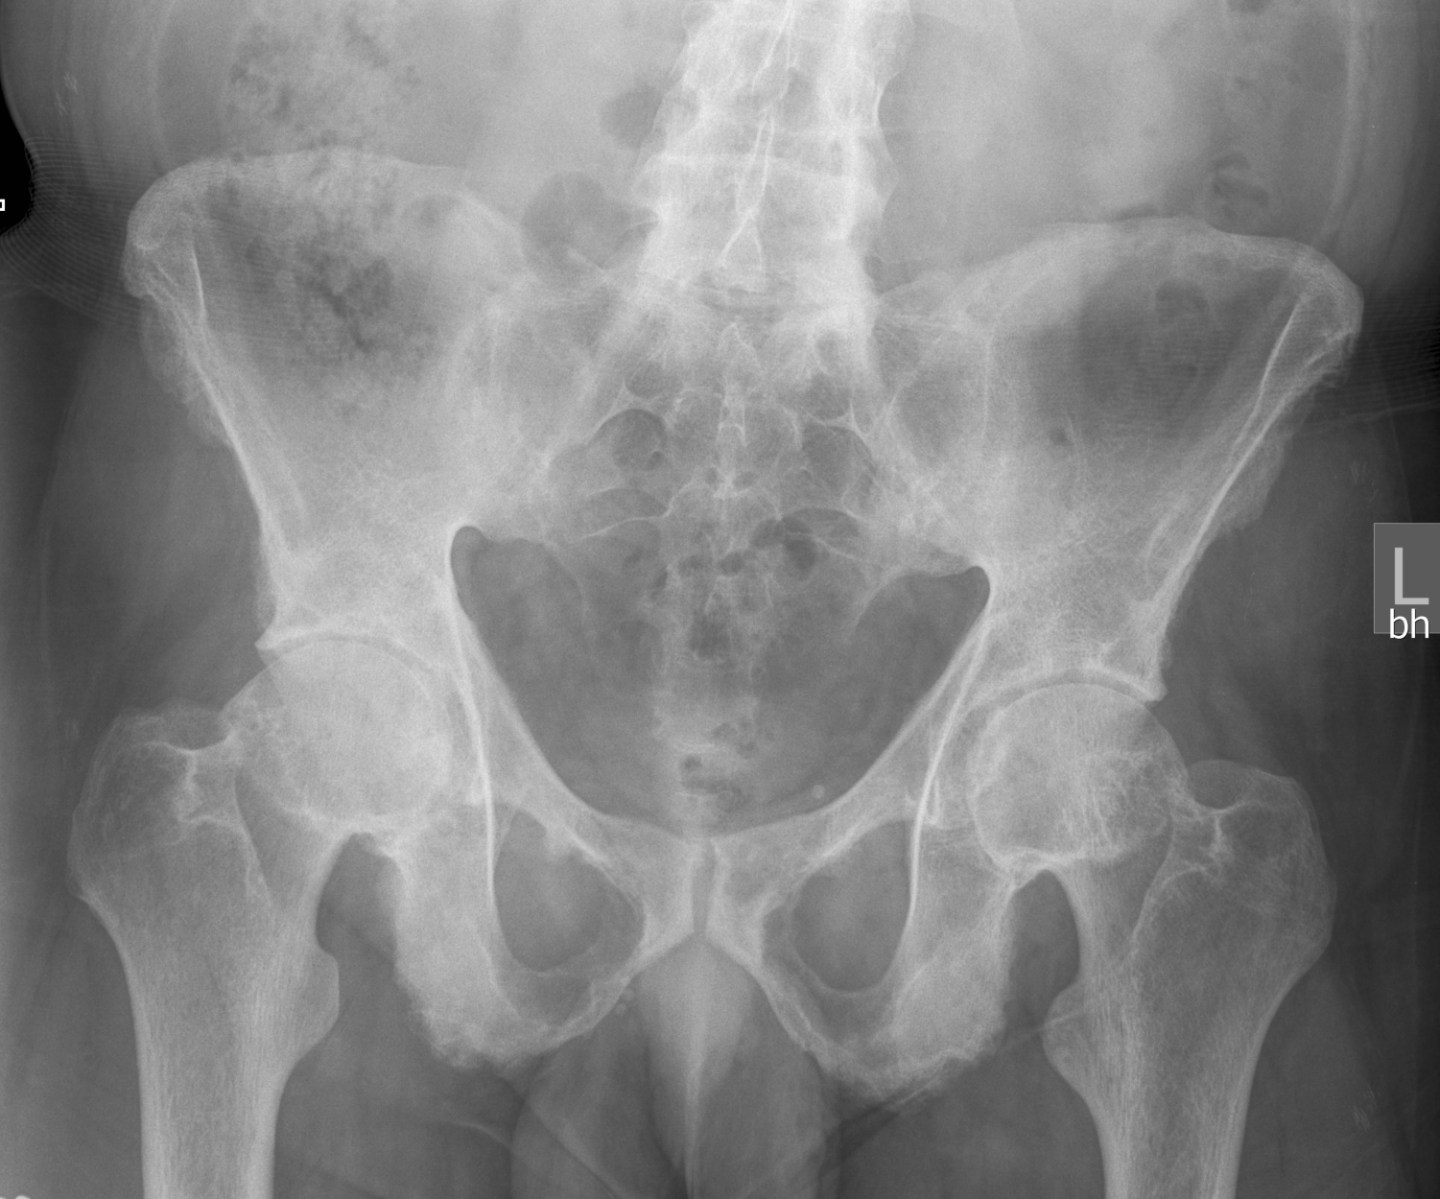

Purpose: Identify individuals presenting with low back/pelvic pain originating from the sacroiliac joint.

Stage of CPR Development: Validated.

Rule:

| Laslett et al., 2003/05 | van der Wurff et al., 2006 |

| SI Distraction | SI Distraction |

| SI Compression | SI Compression |

| Thigh Thrust Test | Thigh Thrust Test |

| Gaenslen’s Test | Gaenslen’s Test |

| Sacral Thrust | Patrick’s Sign (FABER) |

Interpretation (3+ Variables):

| Study | Sensitivity | Specificity | +LR | -LR |

| Laslett et al., 2003 | 0.91 | 0.78 | 4.16 | 0.12 |

| Laslett et al., 2003 (Excluding Centralization) | 0.91 | 0.87 | 6.97 | 0.11 |

| Laslett et al., 2005 | 0.94 | 0.78 | 4.29 | 0.80 |

| van der Wurff et al., 2006 | 0.85 | 0.79 | 4.02 | 0.19 |